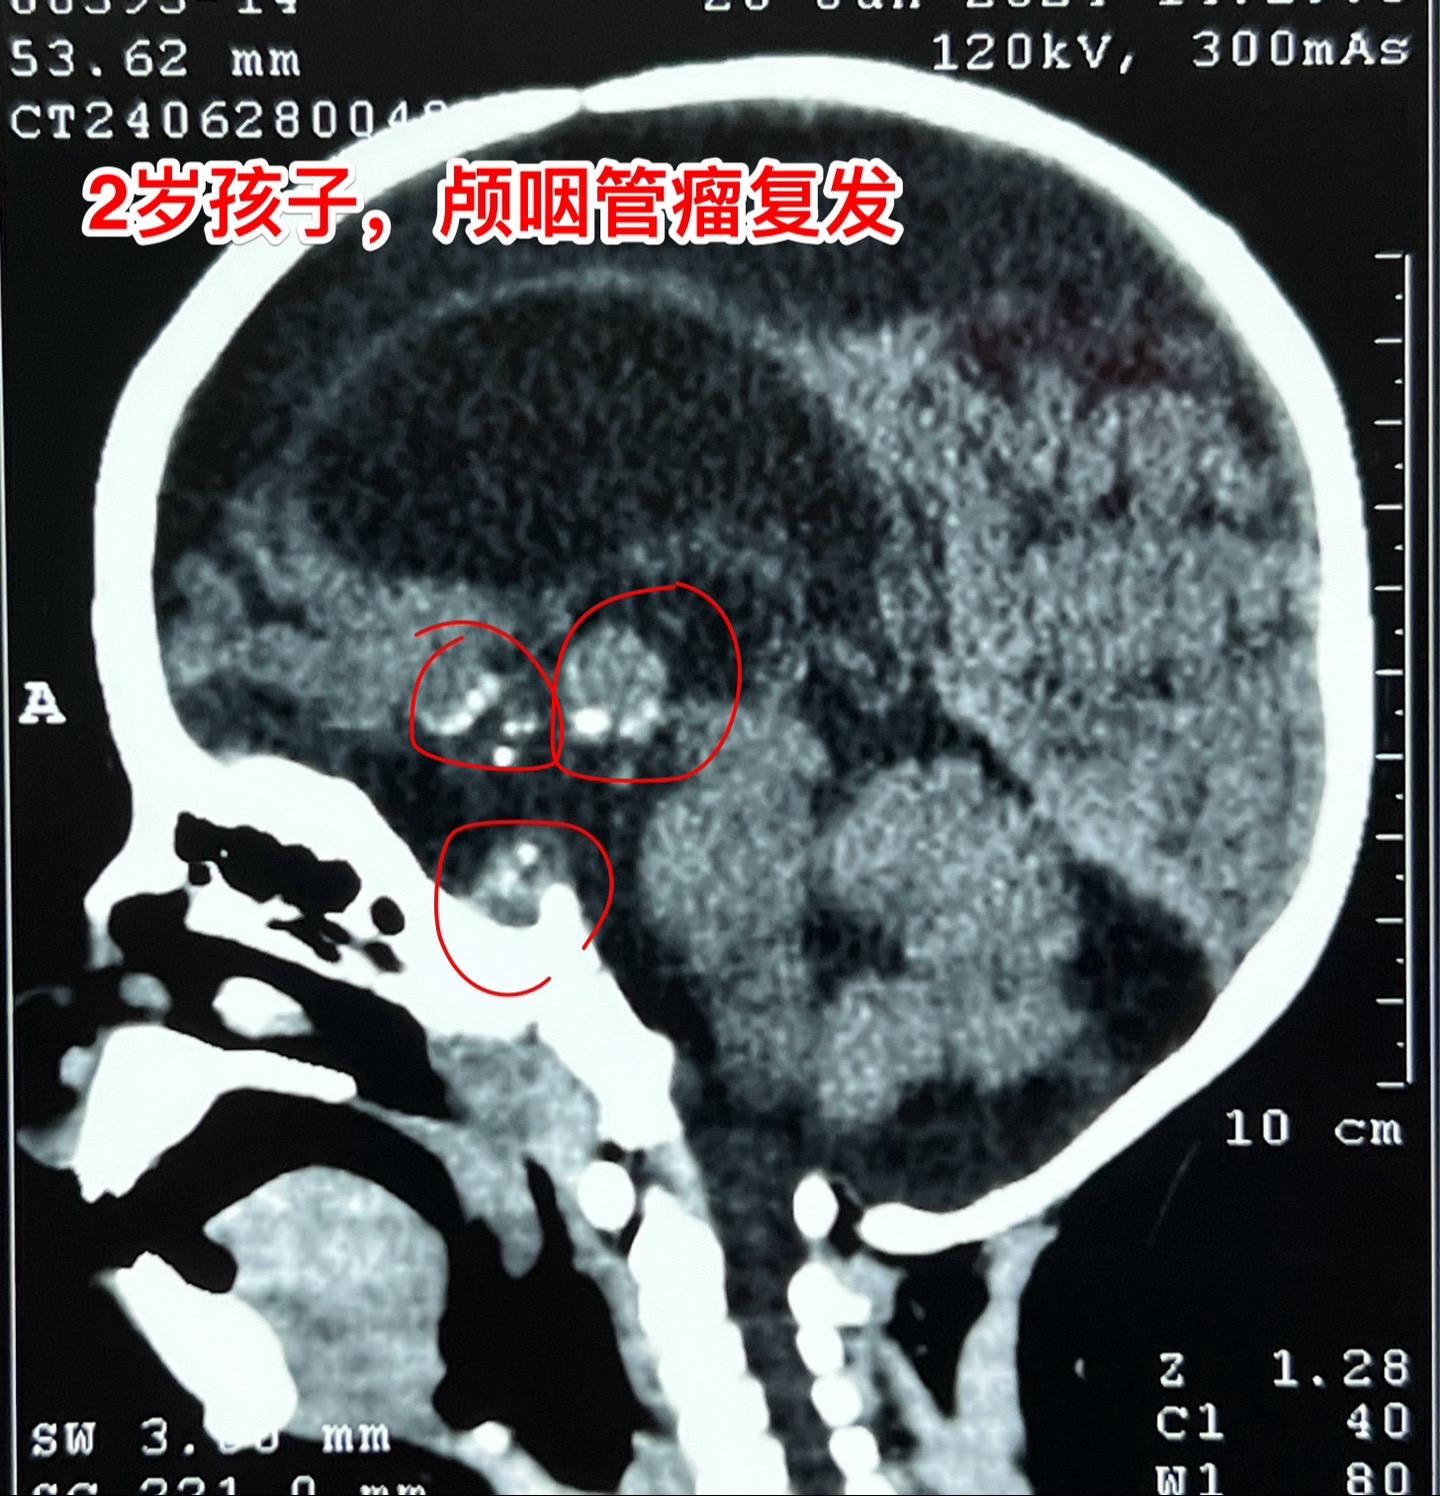

16岁女生颅咽管瘤第三次手术。第二次手术是在2013年1月。那次手术后还因脑积水作了脑室腹腔分流术。出院后能上学读书,而且内分泌方面还不错。有点遗憾的是额部手术疤痕及颅骨变形影响了病人的容貌。 这次的手术原计划在5月28日进行,因为她的生理周期突然提前了(自然的周期)故而将手术推迟到6月4日进行。肿瘤得到完全切除。 这次的肿瘤体积很大,但是还没有影响到垂体-下丘脑,可以预见,她的内分泌功能不会受到破坏。只希望她的肿瘤不再复发。内分泌 2024-06-07 09:07